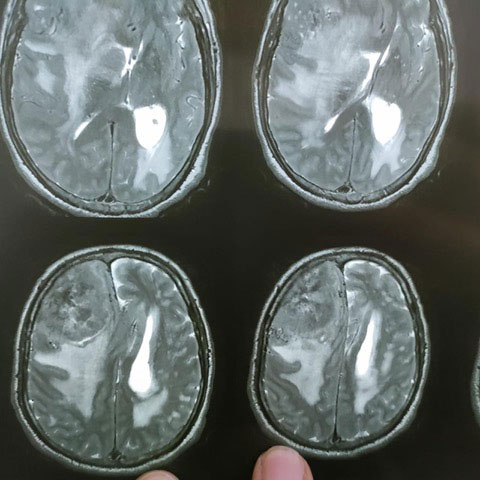

Surgical Highlights